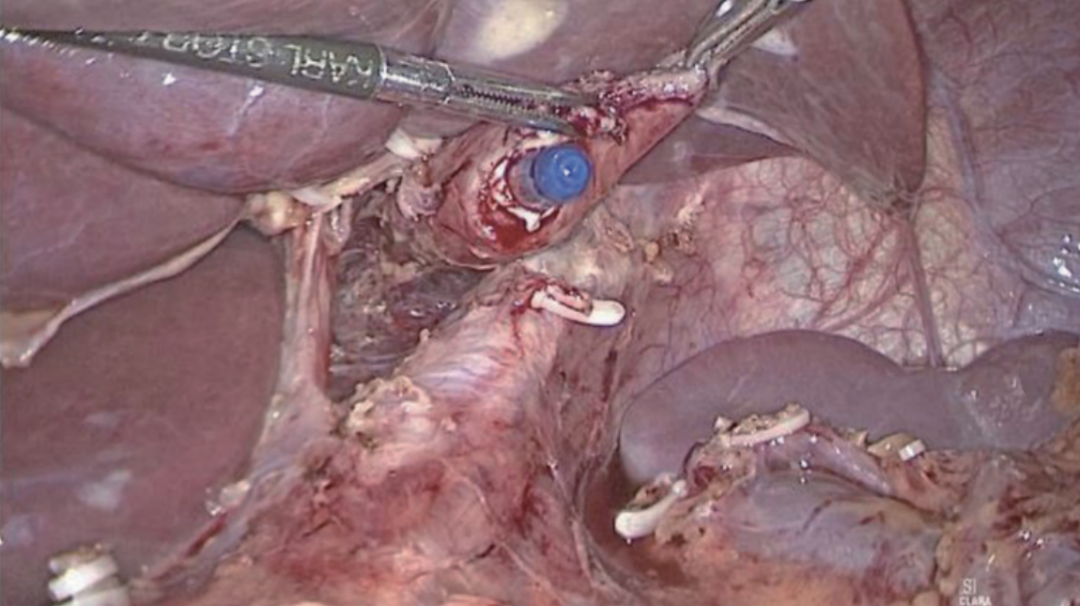

切开食管残端左侧角(图20),将直线吻合器钉仓臂插入远端空肠断端对系膜缘小口(图21),并在胃管引导下将抵钉臂插入食管残端左侧角开口(图22),行食管-空肠逆蠕动侧侧吻合,即功能性端端吻合(FETE吻合),用直线切割吻合器关闭共同开口(图23)。FETE吻合要求共同开口的关闭方向与食管空肠的切割闭合线或空肠长轴垂直,以预防出现吻合口狭窄。为了更好关闭共同开口,预缝共同开口3针作牵引(图24)。

图21 远端空肠残端插入吻合器钉仓臂

图22 在胃管引导下将吻合器抵钉臂插入食管腔内

图23 关闭食管空肠共同开口